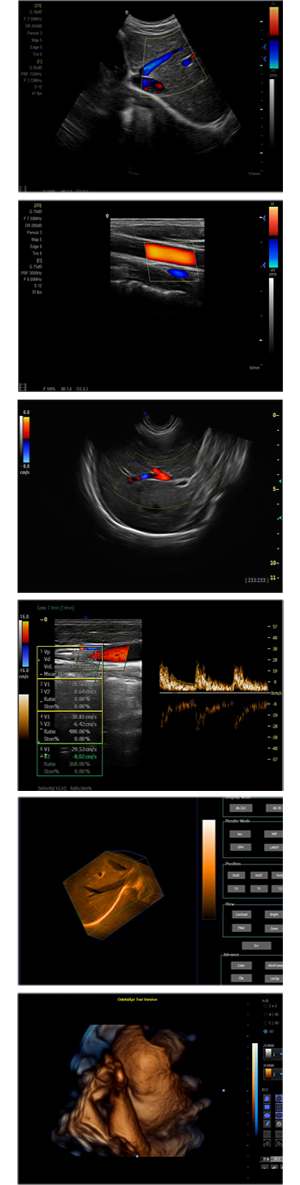

XF-7700型,秉承先鋒彩超技術(shù)之精華,擁有高雅大氣的獨特外型,為最新一代應(yīng)用型數(shù)字彩色多普勒診斷系統(tǒng),魅力與實力相融合??蓮V泛適用于腹部、婦產(chǎn)科、心臟、小器官、乳腺、肌骨及外周血管等諸多方面的診查,讓您在臨床超聲診斷應(yīng)用領(lǐng)域得心應(yīng)手,綻放異彩!

突破的成像技術(shù)

● 3D/ 4D成像技術(shù)/選配

● 應(yīng)用于腹部、腎臟、泌尿系統(tǒng)、產(chǎn)科、婦科、盆腔、大動脈、肌肉組織、小器官、乳腺、心臟等

● 能量多普勒成像(PDI)

● 彩色血流量圖(CDE)

● 脈沖頻譜多普勒成像(PW)